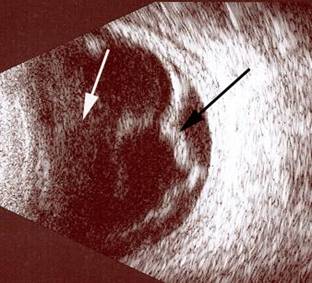

Resim 1: Normal retina fotoğrafı. Renginin her tarafta homojen olarak pembe olduğu, damarların ( beyaz ok ), ve göz sinirinin ( siyah ok ) net olarak seçildiği görülmektedir.